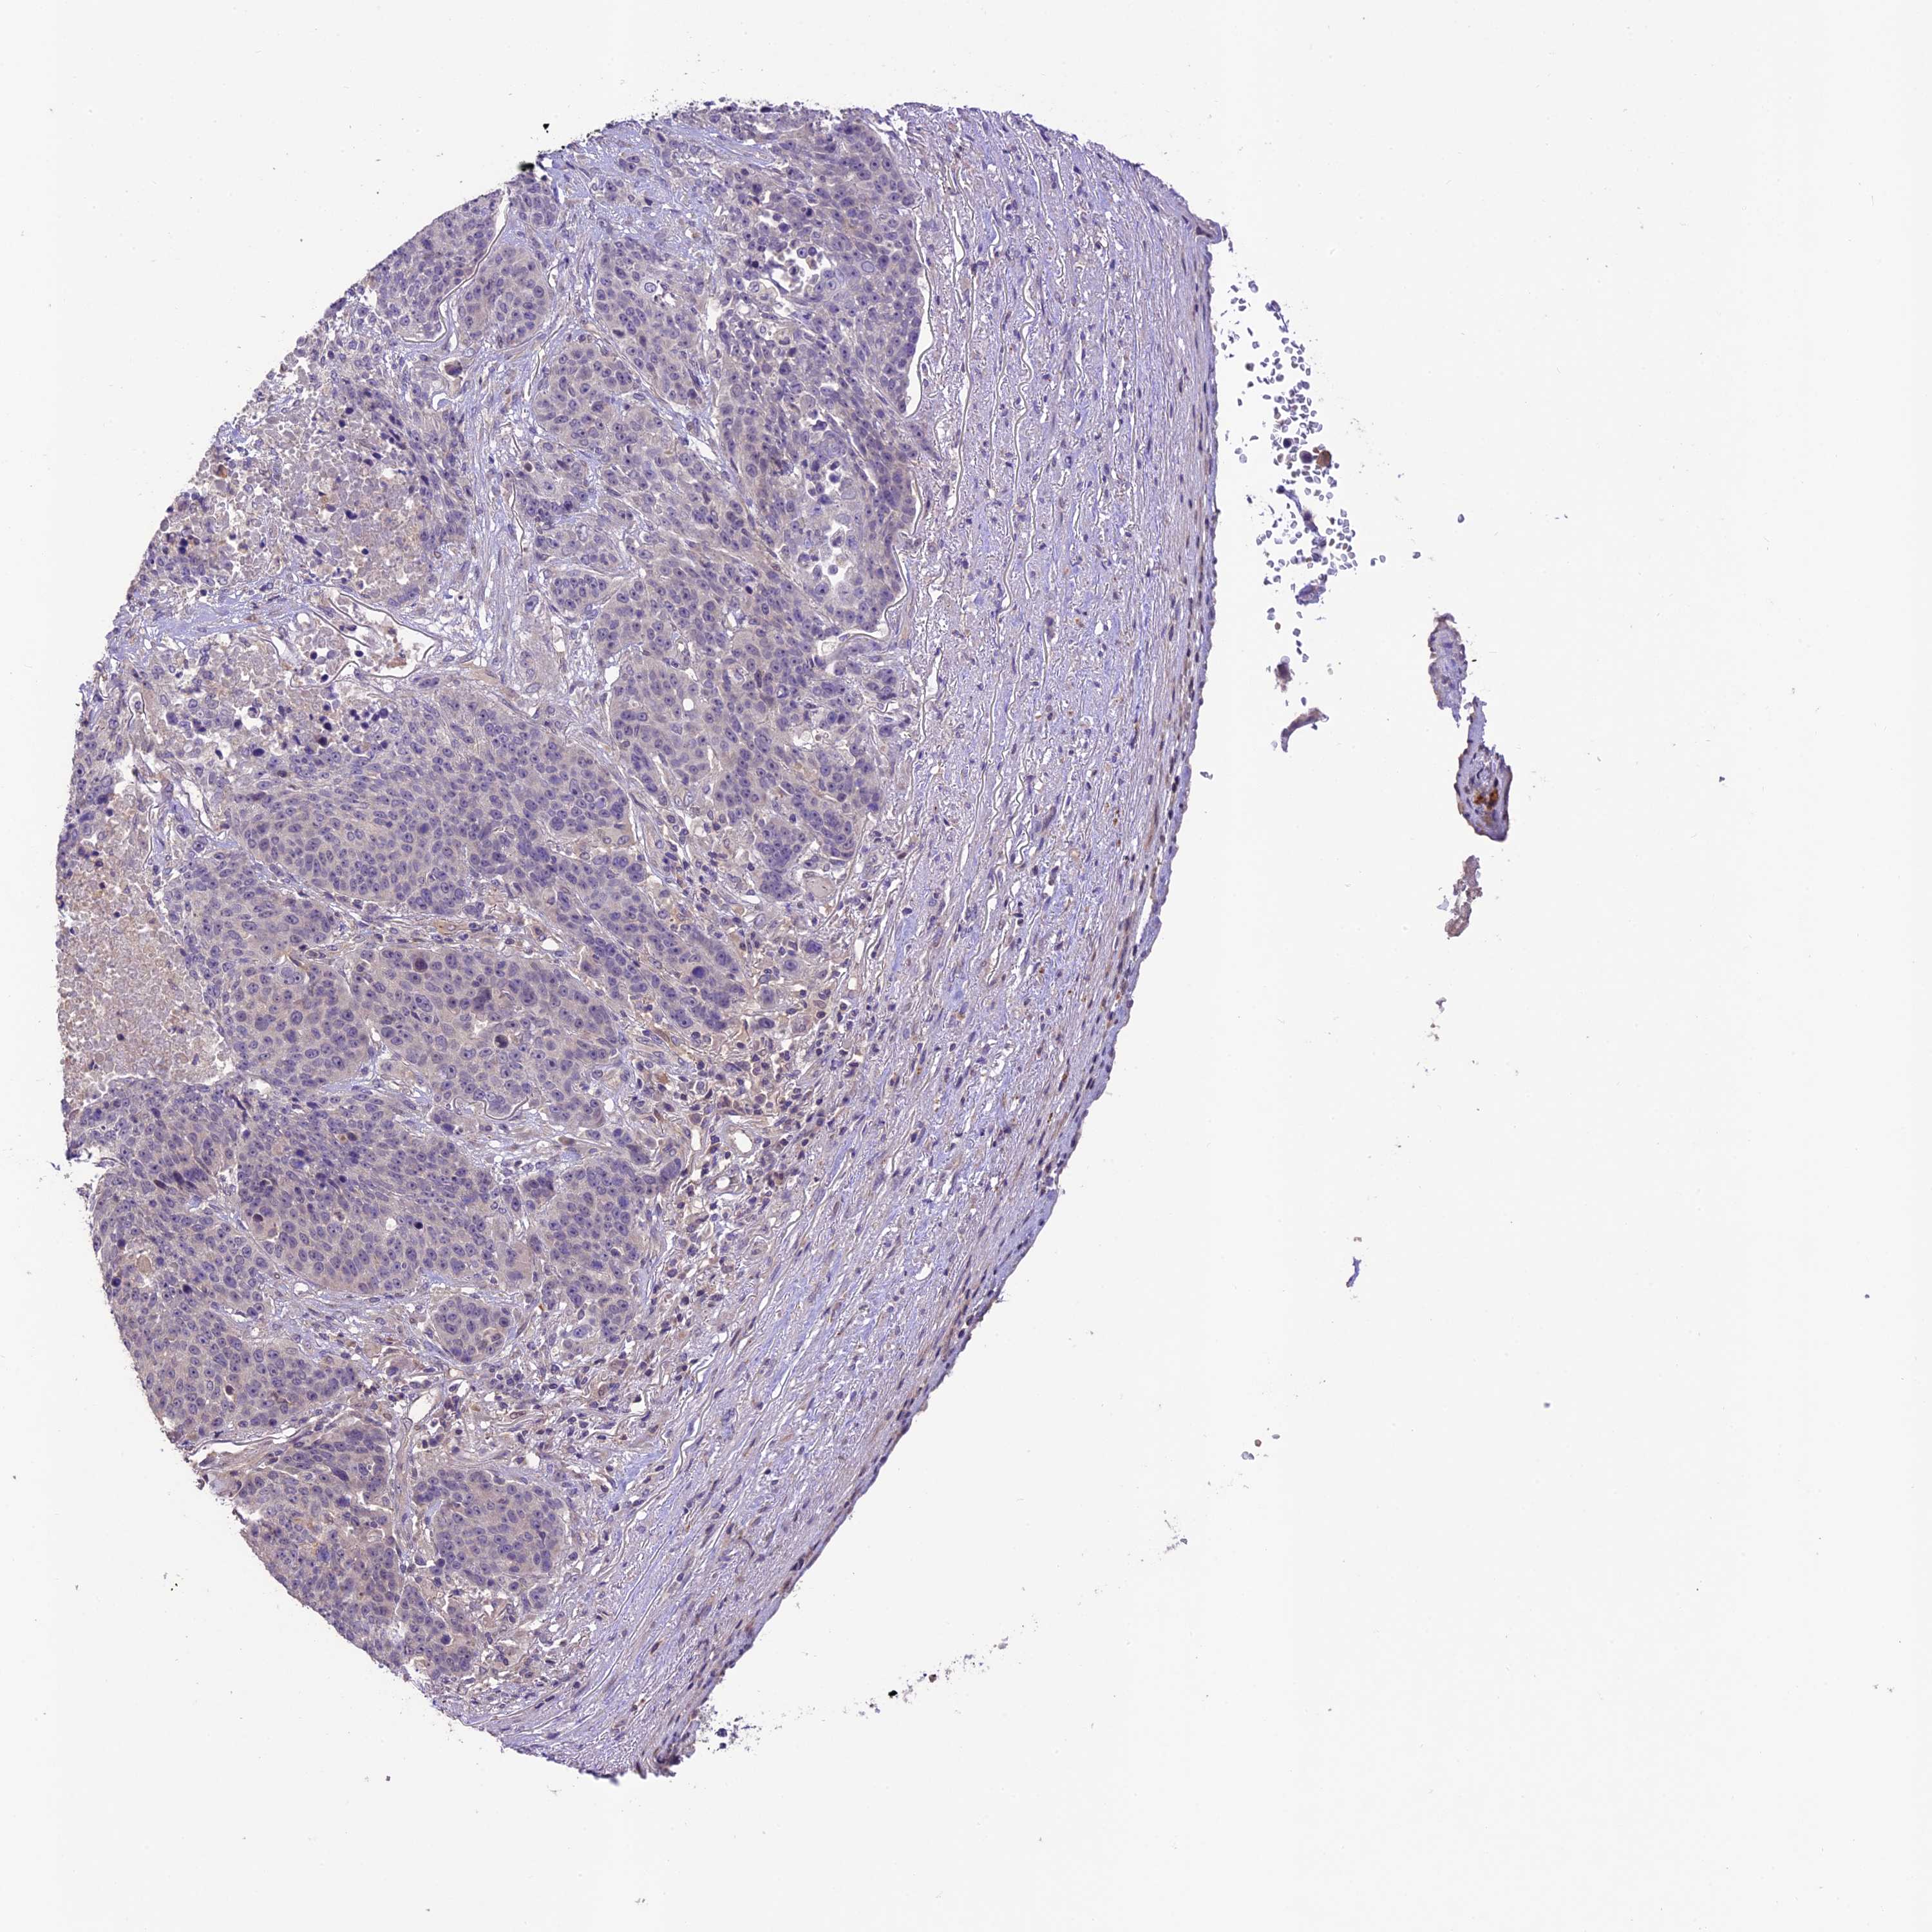

CANCER LUNG CANCER Show tissue menu

Lung cancer

Human cancer